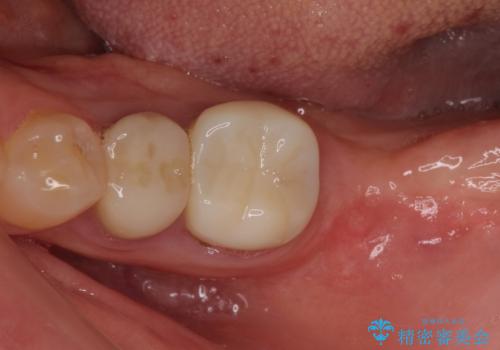

- 抜歯が必要と診断された奥歯の治療を希望して来院された患者様です。

一番奥の歯は歯根の一部を残した状態で、手前の歯とブリッジが装着されていました。

奥歯は歯根周辺の歯槽骨が広範囲に失われており、抜歯が必要と判断されました。

ブリッジの手前側の歯は、根管治療が必要な状態でした。